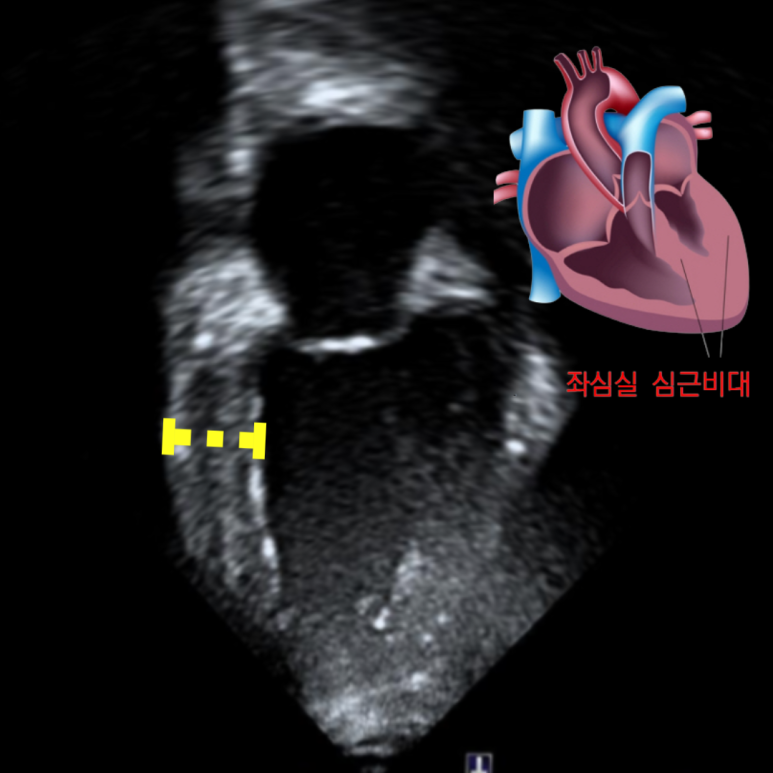

오랫동안 고혈압을 가지고 계셨지만 관리하지 않으셔서 심부전(심장기능저하)가 나타난 환자분 심장초음파 결과